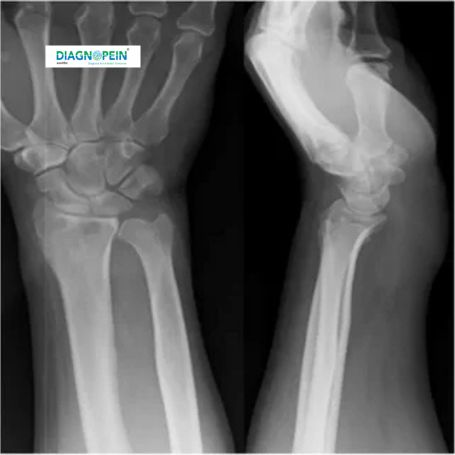

The Both Wrist AP (Anteroposterior) View X-Ray is a diagnostic imaging procedure that helps examine the bones, joints, and structural alignment of both wrists. It provides a clear front-to-back view of the wrist, including the radius, ulna, and carpal bones. In Nashik, Diagnopein offers advanced radiology services with precise X-Ray imaging techniques for accurate diagnosis and quick reporting.

This test is most often recommended by orthopedic specialists and general physicians for patients experiencing wrist pain, swelling, restricted motion, or injury. By capturing both wrists in a single frame, the radiologist can compare bone structures and identify possible abnormalities efficiently.

The Both Wrist AP view plays a critical role in identifying a wide range of conditions that affect wrist health. It enables doctors to accurately detect:

1. Fractures or bone dislocations

2. Arthritis or joint degeneration

3. Bone deformities and alignment issues

4. Inflammatory or infectious bone diseases

5. Post-surgical healing assessment

This imaging view ensures symmetry comparison between the left and right wrists, which helps in evaluating congenital deformities or injury recovery progress. At Diagnopein, Nashik, our expert radiologists ensure every X-ray is taken with high resolution and minimal exposure for patient safety.